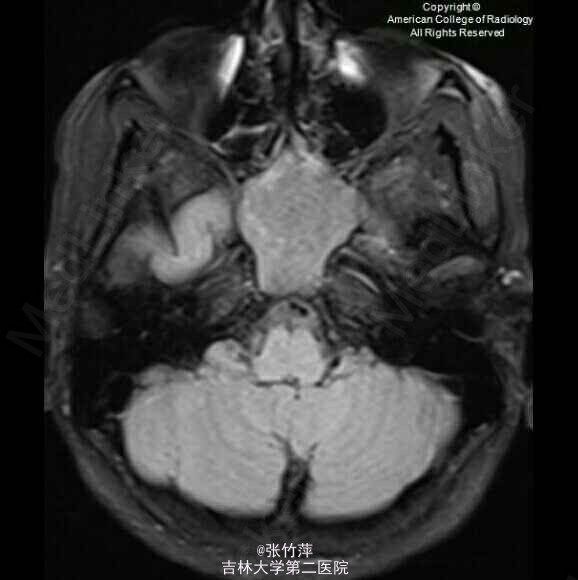

女,20岁。头痛一月余,伴复视,流泪,视力下降。

脑部磁共振图片如下

蝶窦粘液囊肿